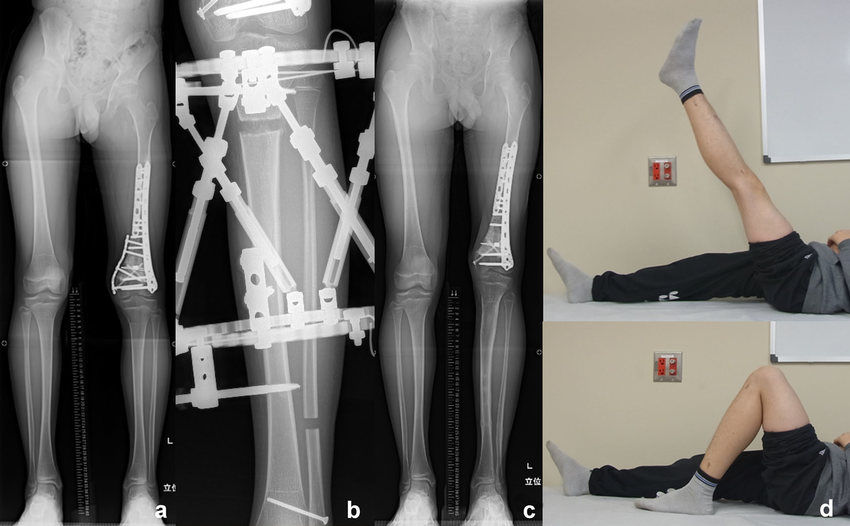

• *Limb Lengthening*: Involves cutting the bone and gradually lengthening it using an external fixator or internal lengthening device. This is a lengthy process but can effectively correct significant discrepancies.

• *Ilizarov Technique*: A specialized external fixator technique used for limb lengthening and correction of complex deformities.